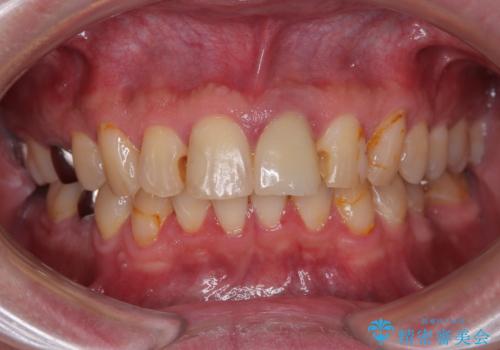

- 前歯の見た目を良くしたいとのことで来院された患者様です。今までに保険のプラスチック(コンポジットレジン)で虫歯の治療をしており経年的な劣化により着色が目立つようになっていました。また歯と歯の隣り合っているところに段差もあり虫歯になっていたり、詰め物も外れていたため前歯4本のオールセラミッククラウンによる治療を行うこととなりました。